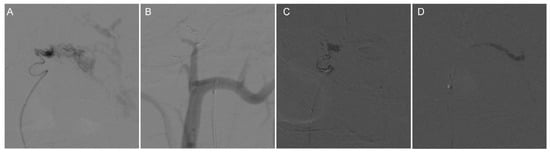

Figure 3.

Intraoperative DSA angiographic treatment of CCJAVF. (A) Microcatheterization through the superior trunk of the ascending pharyngeal artery to reach the lesion; microcatheterization was performed to clarify the fistula. (B) Spring coil embolization of the fistula via the microcatheter; (C) The first microcatheter located in the superior trunk of the ascending pharyngeal artery was used to occlude the fistula with a biologic gel; (D) The second microcatheter in the lower trunk of the ascending pharyngeal artery was used to occlude the fistula with a biologic gel.